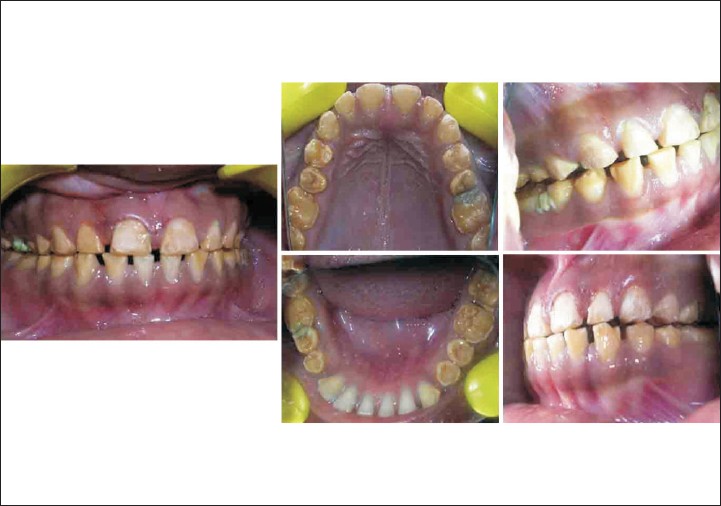

In case D, patient had loss of vertical dimension of occlusion and patient's inter-occlusal space was 4mm at rest. Therefore a treatment plan was evolved to increase the vertical dimension of occlusion by 4mm which was within the limit for the patient. [20] Full mouth restorations were planned with metal ceramic crowns. This treatment option of restoring vertical dimensions of occlusion for severe fluorosis patients requires careful investigations and preparation. This treatment option is limited to cases with severe fluorosis and loss of inter-occlusal space. Advantage of this procedure is that it is an extensive procedure by which the desired aesthetic results and functional efficiency is achieved. The main disadvantage is also its extensiveness in treatment procedure which requires extensive lab procedure and operator skill, knowledge.

In each of the treatment options described above, each one has its own advantages and disadvantages; a good clinician should be aware of all the treatment options available assess its merits and demerits and select the best treatment option according to individual patient needs.